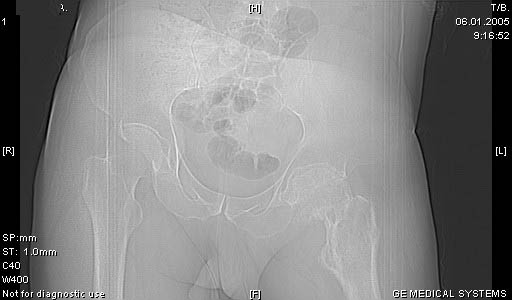

И снова вопрос по эндопротезированию: Пациенту 51 год. Болен с 2000 г, когда отметил умеренные, нараостающие боли в в/3 левого бедра, прогрессирующую контрактуру лев Т/Б сустава.

05.12.04 после падения на бедро боли резко усилились, нога стала неопорной. На рентгенограмме обнаружен патологический перелом шейки бедренной кости. Обследован в отделении костной онкологии. Результат биопсии: асептический некроз проксимального отдела бедренной кости. Вопрос: выбор технологии эндопротезирования - цементная или бесцементная версия. Заранее благодарю! С уважением,А.В.Владзимирский

Как то очень подозрительно выглядит проксимальный отдел бедра для такого очень простого гистологического заключения. Вы уверены, что гистология настолько благополучна и в каком варианте она выполнялась: пункционная или открытая с забором костного блока? Не уверен на все сто , но область проксимального отдела бедра - одно из излюбленных мест для гигантоклеточной опухоли, которая зачастую озлакочествляется (имел два подобных наблюдения). Из своей практики могу сказать, что, к сожалению, информативность пункционной биопсии не сравнима с открытой техникой. Поэтому прежде чем решать цементный или бесцементный протез использовать, я бы повторил биопсию в сочетании со сканированием скелета, сывороточная щелочная фосфатаза, кальций, фосфор сыворотки, СОЭ, С- реактивный белок,

Soglasen s Евгений И Чекашкин, proximal Femur does not look right. Sarcoma? Pagets, Osteomyelitis?. Technicality of the implantaion will be dependent upon underlying pathology, and the surgeon's level of comfort.